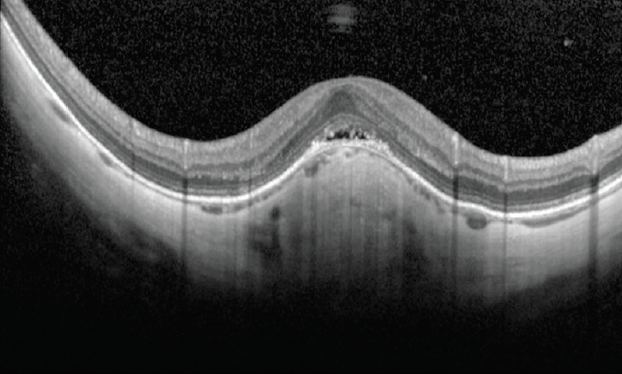

Figure 1. SS-OCT scans showing variation of choroidal thickness in chorioretinal diseases. A thickened choroid is shown in a patient with CSCR (A), and choroidal thinning in a patient with AMD (B).

Choroidal Thickness

Choroidal thickness varies among disease states, and the choroid becomes thinner with increasing age and axial length.7 Choroidal thickness is increased in central serous chorioretinopathy (CSCR), polypoidal choroidal vasculopathy (PCV), and Vogt-Koyanagi-Harada syndrome but is decreased in age-related macular degeneration (AMD) (Figure 1).8-10 Choroidal thickness decreases from the macular area to the periphery and is at its maximum subfoveally and in the superior quadrant.11